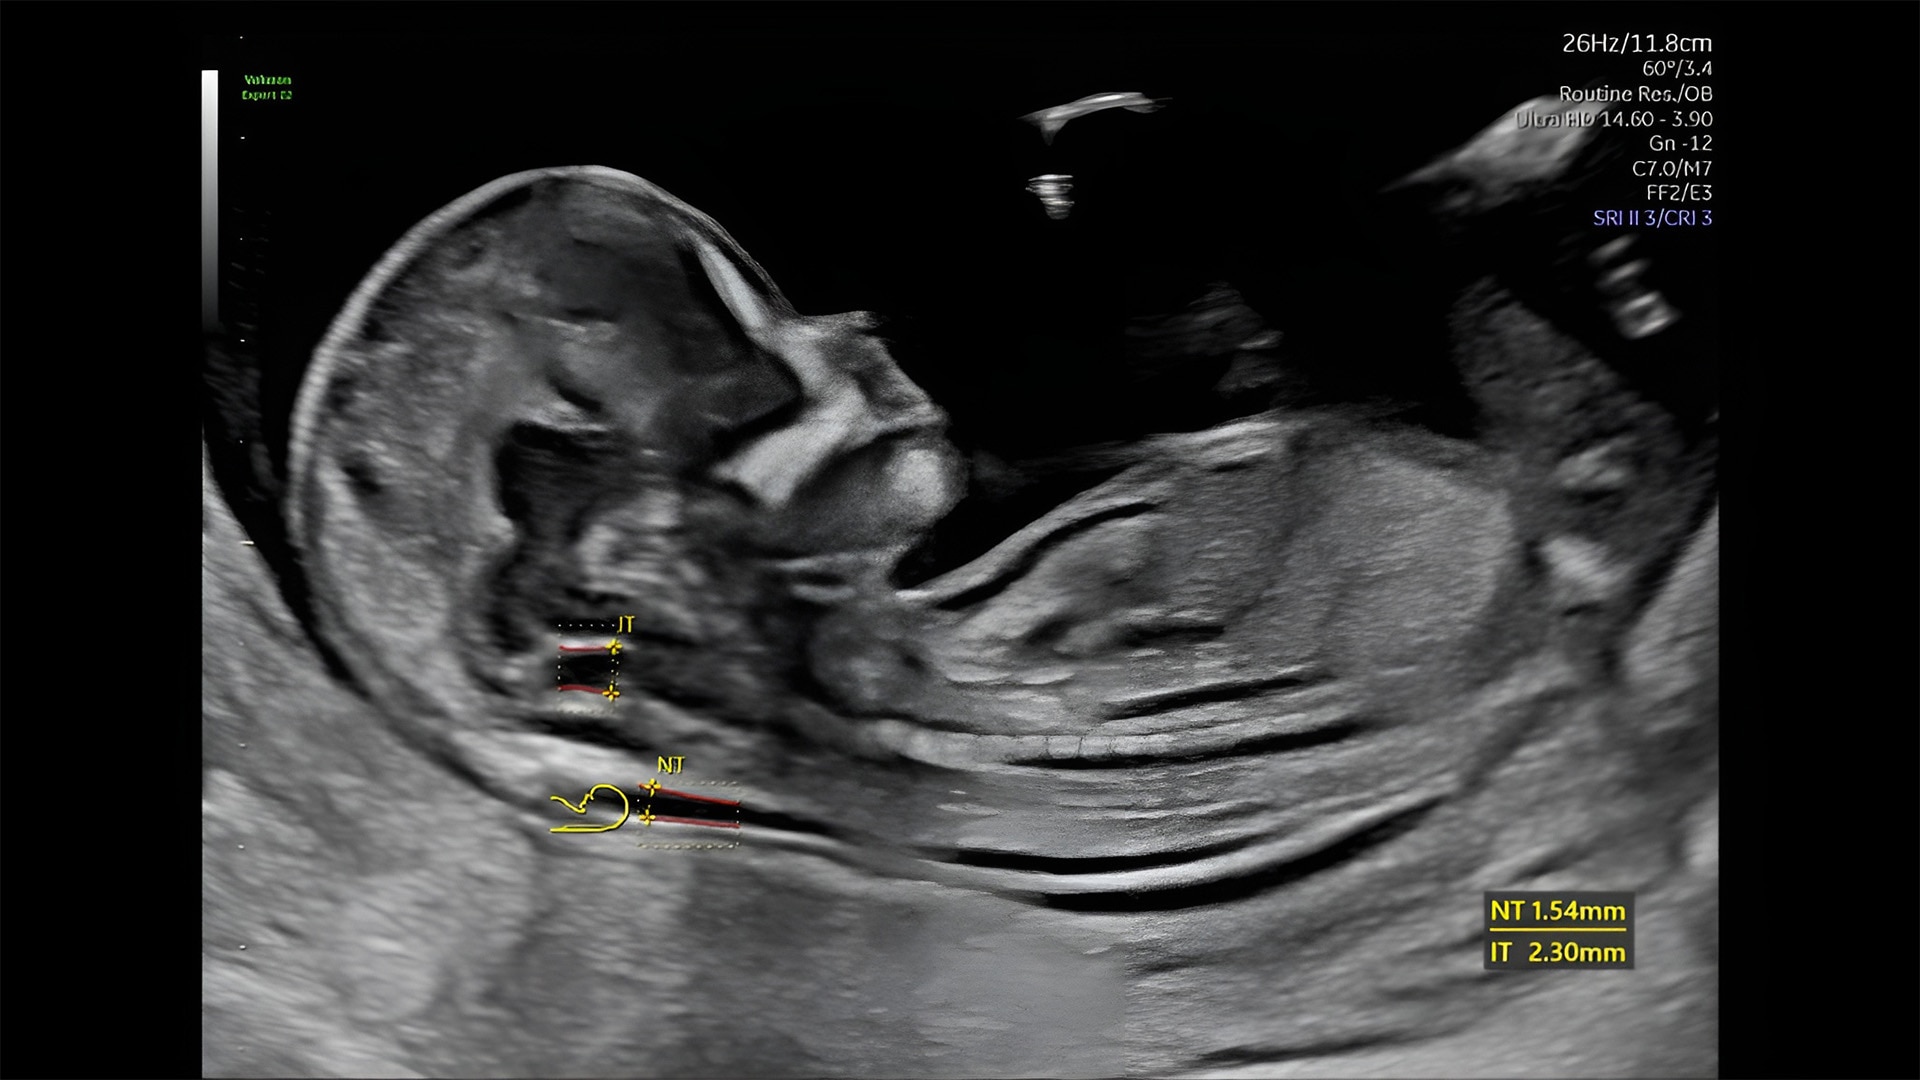

First trimester exams

Perform detailed exams with high-resolution for early insights to fetal health